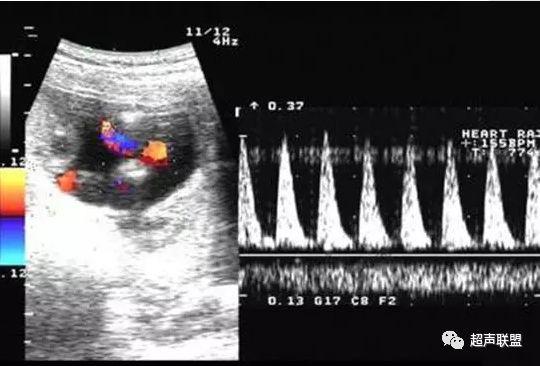

2 胎儿大脑中动脉测定

缺氧早期大脑血液供应增加,颅内血管扩张,阻力降低,舒张末期血流速度增加,PI、RI值下降,说明缺氧早期的血流再分配。当大脑中动脉RI、PI值明显下降,而脐动脉和腹主动脉的PI值升高,大脑中动脉PI值与脐动脉PI值的比值低于2个标准差时,提示严重缺氧的存在。

图3 正常大脑中动脉血流频谱

图4 大脑中动脉血流阻力减低